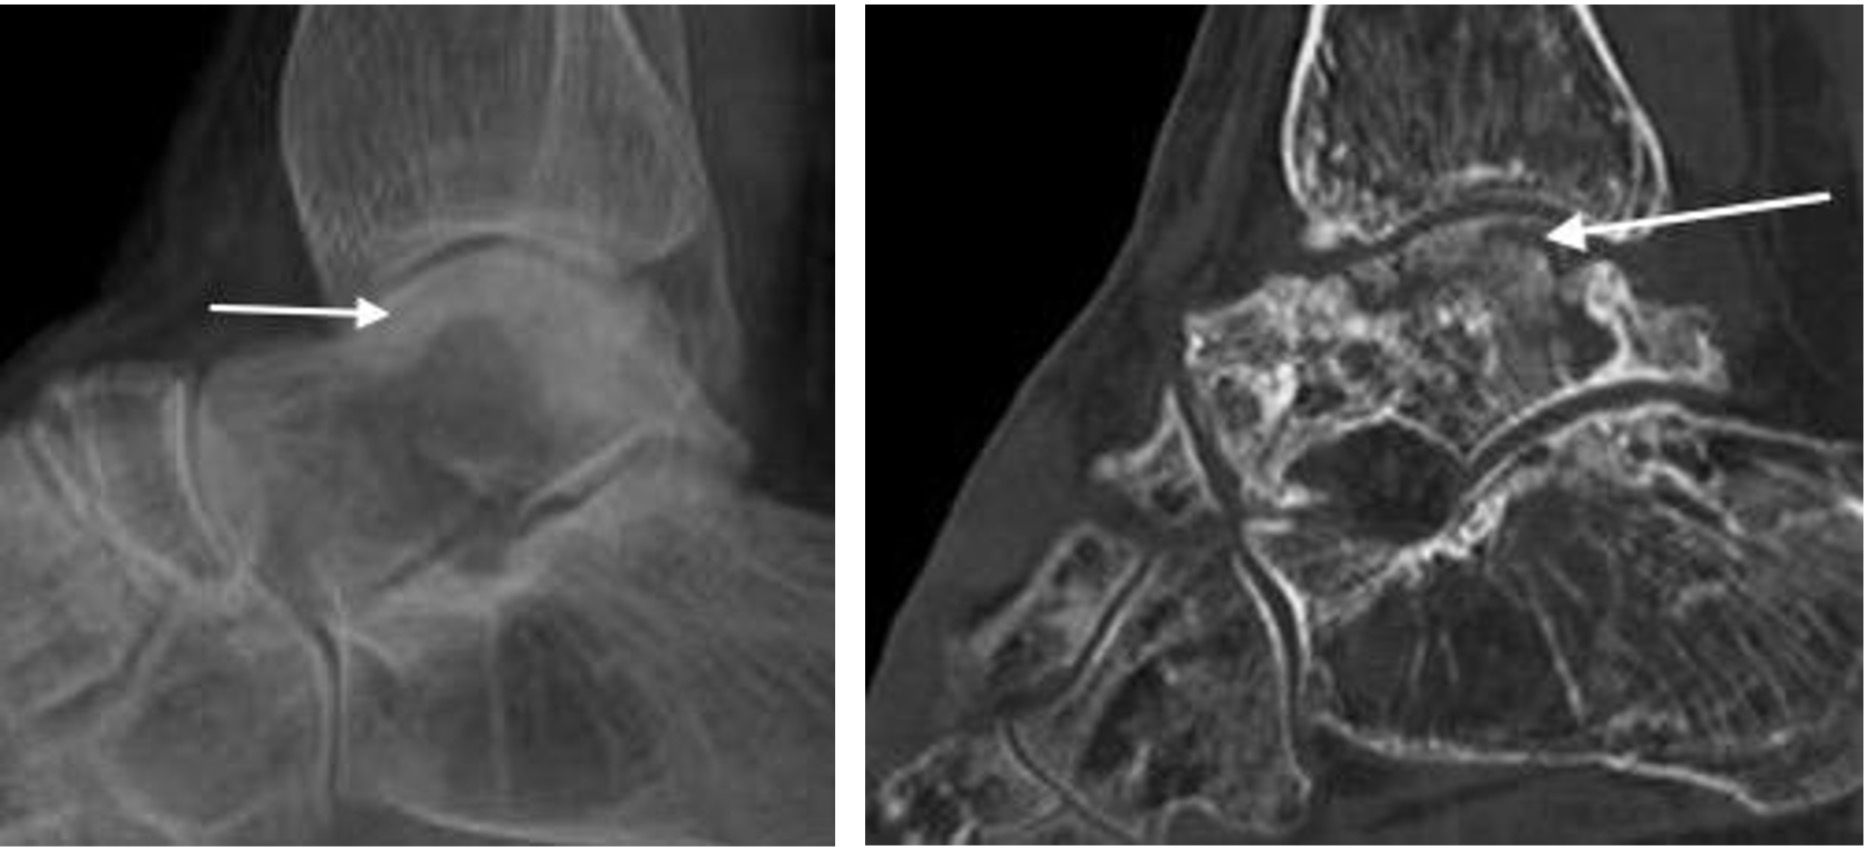

Infected nonunion subtalar joint (arrow)

Avascular necrosis of the alar dome following talar neck fracture with subchondral sclerosis and fracture (arrows). Note disuse osteopaenia.